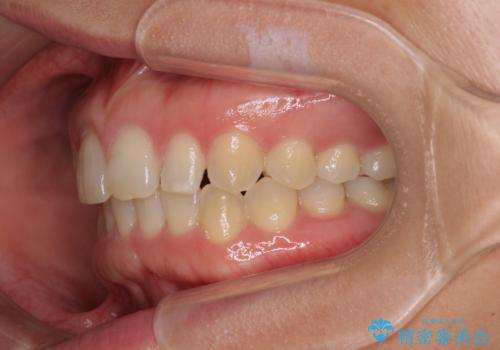

前歯の歯並びと小さい歯を改善 インビザラインとオールセラミッククラウン

- 前歯の空隙と矮小歯を気にして来院された患者様です。

上下の歯列不正はインビザラインにより整えることとしました。

矯正治療の後に、前歯1歯と奥歯をオールセラミックにて治療することとしました。

矯正治療により矮小歯前後にスペースを作りながら歯列を整え、セラミッククラウン装着後に最終的に歯列と咬合を仕上げました。